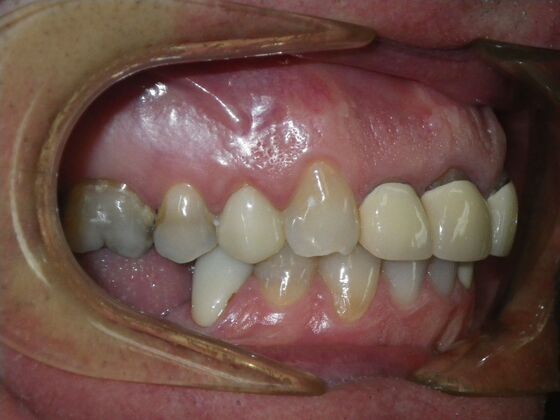

Cosmetic Changes with Veneers and Crown and Bridge: Case 5

Patient wanted to see about getting his upper front crowns replaced. He has had them for 35 plus years. Also concerns about his gums receding and the metal margins of crowns showing. Also talked with him about the need for crown lengthening which would have helped decrease the gummy smile; however, he chose not to do this. I thought just replacing the existing crowns to the existing gingival margins would be a great help. So the existing porcelain/metal crowns were removed and new all ceramic single unit crowns placed from upper right cuspid,lateral incisor and right central incisor. Then a 3-unit all ceramic bridge was placed from upper left central incisor to upper left cuspid. This patient and most of all his wife were very pleased with the end result.